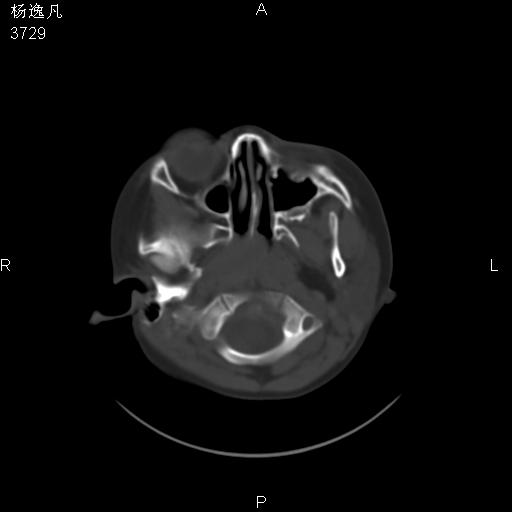

男性,5岁,面部受外伤,余无特殊

骨窗

位置太不标准了!

头颅ct平扫未见明确外伤性征象,右侧面部及颞部软组织肿胀,后鼻腔软组织影增大,增厚,鼻咽顶部变窄,考虑鼻咽腺样体增值肥厚。

双侧位置太不对称,未见明显骨折征象。

还是重建了再看吧。还可以看一下始矢状位,了解一下气道的情况。